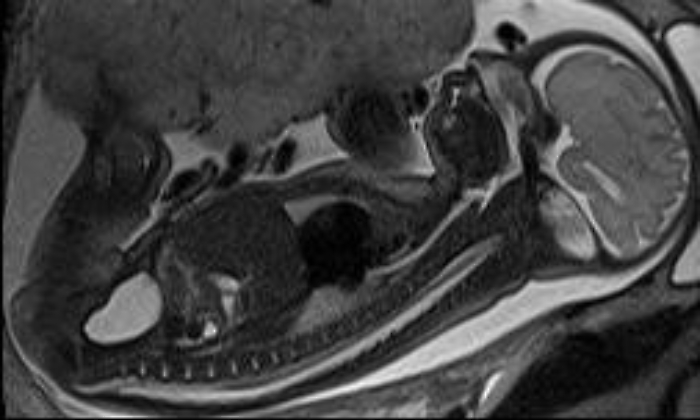

Roma, 28 apr. (AdnKronos Salute) - La tutela della salute inizia nell'utero materno. Al D'Amore Hospital di Taranto è stata eseguita per la prima volta una risonanza magnetica fetale per rintracciare una sospetta patologia cerebrale già diagnostica, su un feto di 19 settimane. E' stata l'équipe di Radiologia, guidata da Maurizio Resta, specializzato nella diagnosi e nel trattamento di patologie in ambito neurologico, a effettuare il delicato esame. "La diagnosi ecografica - spiega Resta - ha accertato una sospetta condizione patologica al cervello del feto e la risonanza magnetica ha chiarito la natura di tale malformazione: questo ha consentito di pianificare il miglior percorso di terapia". "La risonanza magnetica ha assunto un ruolo sempre più cruciale nella determinazione delle anomalie del sistema nervoso fetale, anche in utero - precisa Resta - Diventa fondamentale per il radiologo quando il bebè è ad alto rischio di sviluppare un deficit neurologico". Il principale campo di applicazione della risonanza magnetica fetale riguarda lo studio delle malformazioni del cervello, ma non solo: l'indagine si estende anche alla valutazione delle patologie di collo, torace, apparato gastroenterico e apparato uro-genitale, e di recente anche al cuore fetale. L'esame diagnostico di secondo livello, che sfrutta il campo magnetico, rappresenta infatti un utile complemento alla tradizionale ecografia: è piuttosto articolato perché studia un organismo contenuto nell'utero, analizzando ogni aspetto di un'entità biologica presente in un'altra. "La difficoltà principale nell'esecuzione materiale - prosegue Resta - dipende dalla necessità di inseguire un feto che tende a muoversi. L'esame inoltre è limitato dalle ridotte dimensioni delle componenti anatomiche da indagare". Si tratta tuttavia di un'indagine sicura. "Non ci sono evidenze scientifiche su eventuali danni al bambino dall'esecuzione della risonanza magnetica. L'esame utilizza un campo magnetico e radiofrequenze e non radiazioni ionizzanti, al contrario di quanto accade nella Tac - continua Resta - Le tecniche non invasive di diagnosi prenatale sono andate migliorando sempre più negli ultimi anni, e questo ha consentito di raggiungere risultati più precisi riducendo eventuali rischi causati da emissioni radioattive". Grazie ad apparecchiature all'avanguardia e alla recente introduzione di nuove tecniche di imaging, la Radiologia del D'Amore Hospital si accredita così a centro di riferimento regionale per la prevenzione e la diagnosi di malformazioni fetali attraverso esami specifici di alta complessità in grado di tutelare la salute dei bambini già nell'utero materno. Resta, neuroradiologo di fama internazionale, affiancato da Massimo Donatelli, grazie a una esperienza maturata negli anni anche all'estero, si sono specializzati nell'attività diagnostica che rintraccia precocemente le principali patologie neurologiche, oggi tanto diffuse come ictus, aneurismi e malformazioni arterovenose. Gli specialisti mettono in pratica le metodiche più moderne, come ad esempio la spettroscopia, o la perfusione di risonanza magnetica sul cervello, in grado di individuare anche formazioni neoplastiche di dimensioni molto ridotte.